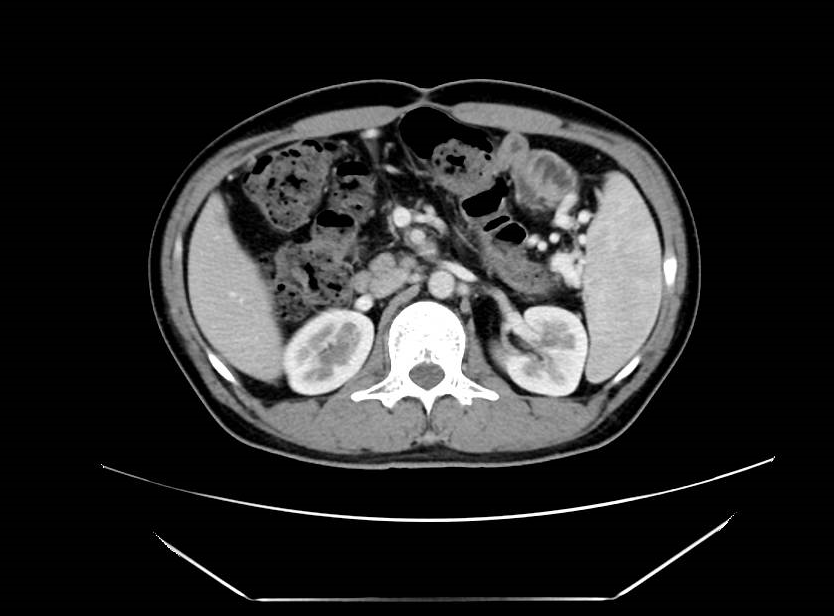

术前CT

术后CT

经过6个周期的精准化疗后,阿杰的肿瘤明显缩小,具备了手术切除的条件。在医生们的努力下,阿杰的手术取得了完满成功。术后7天就基本恢复了自主生活能力。更让人开心的是,阿杰手术6个月后检查,没有发现复发。